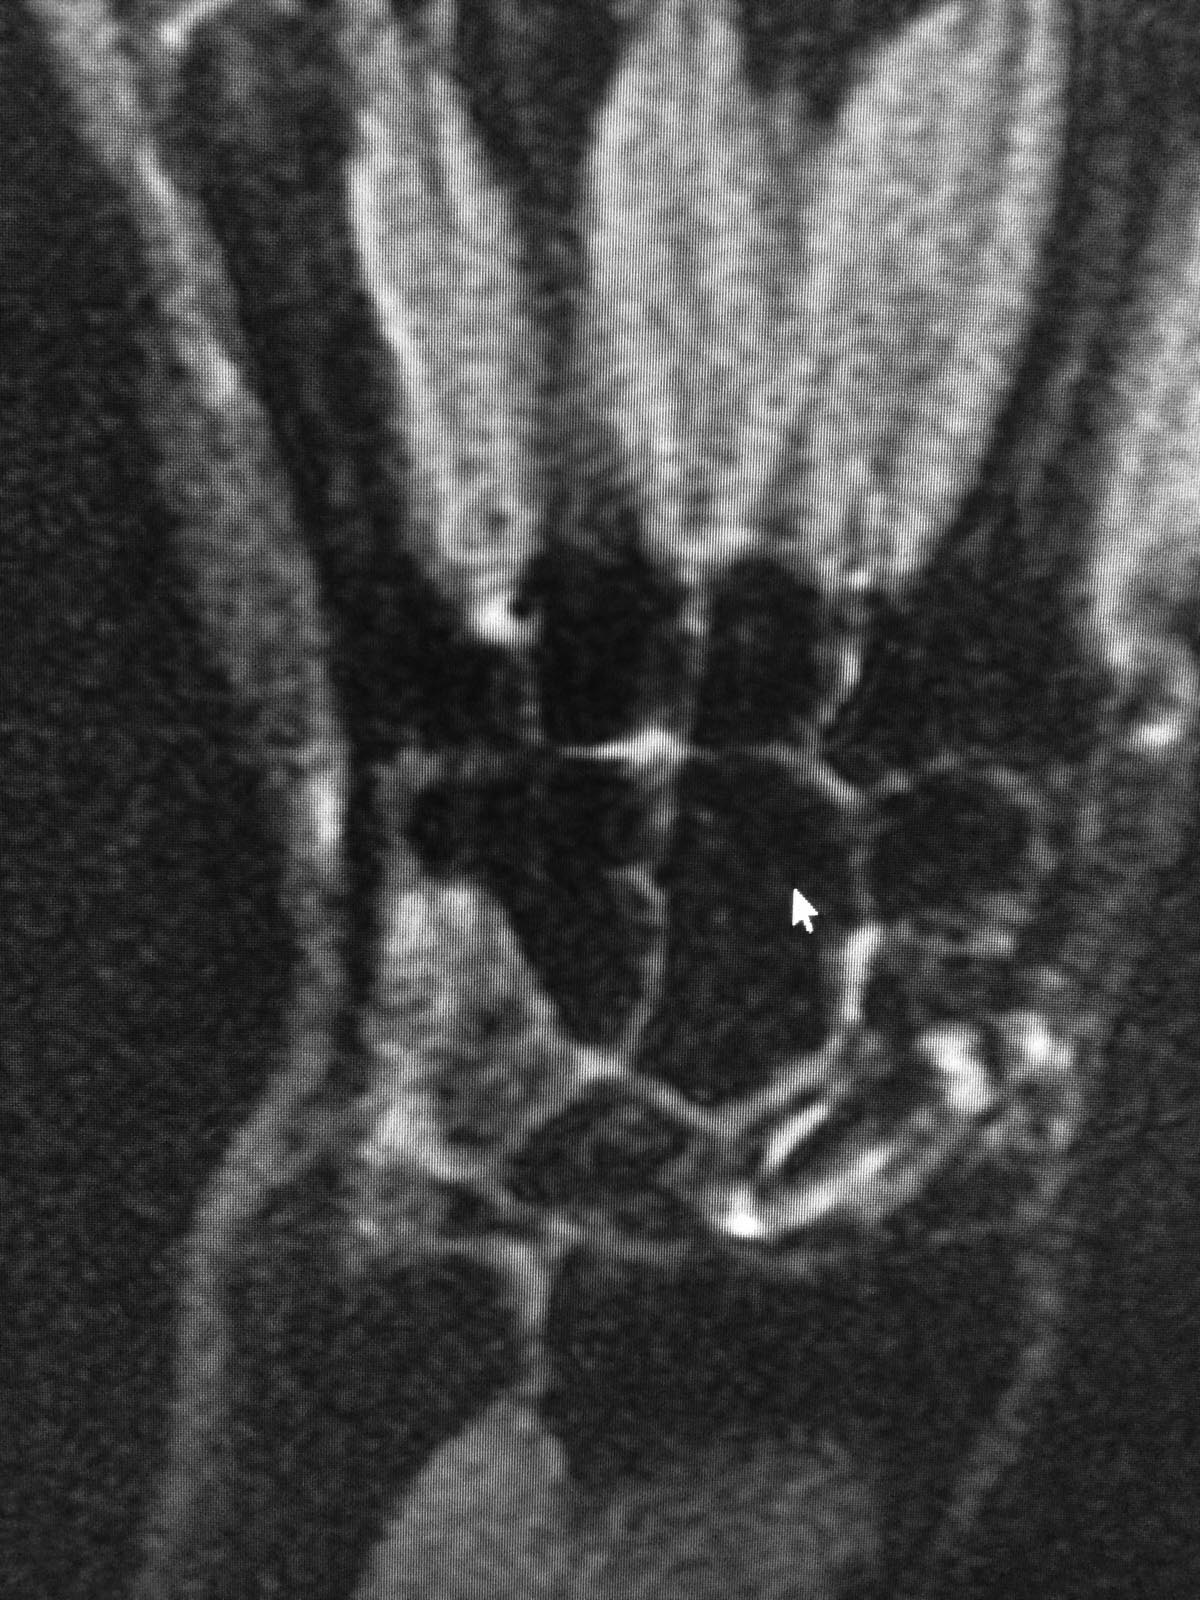

МОС винтом, в данное время в проекции ладьевидной кости болей нет, осевая нагрузка на 1ю пястную кость безболезненная, боли беспокоят при пальпации в проекции трехгранной кости и движениях в лучезапястном суставе(при пассивных и активных движениях возникают острые боли, так же в проекции трехгранной кости). На МРТ отмечаются проблемы в этой зоне. Со слов пациента, при периодических болях принимает таблетку найза, после чего все проходит.

Эльдар, по предоставленным срезам МРТ и описанной клинике сложно судить о состоянии связочного аппарата (в частности полулунно-трехгранной связки) и треугольного фиброзно-хрящевого комплекса (в частности суставного диска), повреждение которых могут давать описанные жалобы. Возможно, в описании МРТ что-то сказано об этом? Что можете сказать о тестах, выявляющих повреждение указанных образований? И все-таки боли возникают периодически или всегда сопровождают движения в кистевом суставе? Болит ли в покое? Андрей, Ваша логика совсем не ясна. Что общего между обсуждаемым пациентом и "стенозом лучевого запястного канала", кроме когда-то сломанной ладьевидной кости? Сергей, с хондроматозом тоже не ясно. Вы его видите на имеющихся снимках? Хондроматоз сустава - показание для удаления одной из образующих сустав костей? SAGo, в сообщении Эльдара нет указания на то, что болит больше всего по тыльной поверхности трехгранной кости.